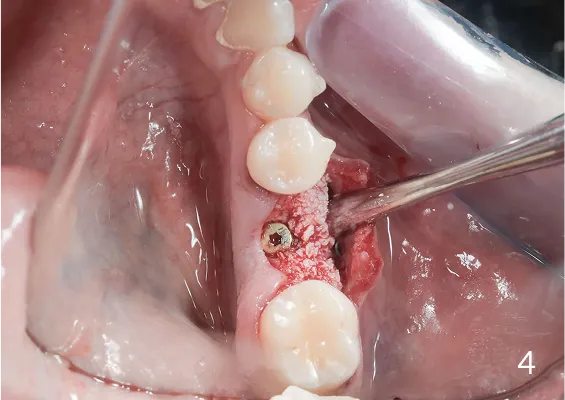

ZABIEGI REGENERACJI KOSTNEJ WOKÓŁ WSZCZEPIANYCH IMPLANTÓW

Sterowana regeneracja kości GBR przy użyciu biomateriałów oraz membran zaporowych. Procedury te są stosowane w sytuacji niedostatecznej ilości kości, skutkującej odsłonięciem gwintu, podczas gdy wszczepiamy implanty stomatolo-giczne lub też jako zabiegi poprzedzające ich wprowadzenie.

To technika pionowego rozszczepienia wyrostka zębodołowego przy użyciu osteotomów. Jest to delikatna technika zabiegowa stosowana w sytuacji braku dostatecznej ilości kości na szerokość. Polega na rozszczepieniu pionowym zanikłego w wymiarze horyzontalnym/poprzecznym wyrostka zębodołowego.

Zabiegu rozszczepienia dokonuje się przy użyciu Piezosurgery, specjalnych zestawów osteotomów lub dłut, którymi rozcina się i rozchyla kość zanikłej części zębodołowej żuchwy lub szczęk.

Pomiędzy rozchylone okładki kostne wprowadza się implanty, uzupełniając materiałem kościotwórczym pozostałą szczelinę w wyrostku. Należy w sposób właściwy dobierać i kalibrować instrumentarium, by nie spowodować uszkodzeń związanych z odłamaniem rozszczepianego fragmentu kostnego.

Regeneracja kostna polega na umieszczeniu w rekonstruowanej okolicy materiału kościotwórczego oraz pokrycie go specjalną błoną zaporową, dzięki której regenerowany obszar chroniony jest przed wrastaniem tkanek miękkich. Po kilku miesiącach na skutek działania procesów regeneracyjnych i remodelujących materiał ulega przebudowie na pełnowartościową, własną tkankę kostną pacjenta, w którą bez obaw można wprowadzić implanty stomatologiczne. Obecnie istnieje wiele innych protokołów regeneracyjnych dla kości, uwzględniających zastosowanie różnego typu błon zaporowych, siatek tytanowych oraz uzyskanych i odwirowanych z krwi autogennych czynników wzrostu.